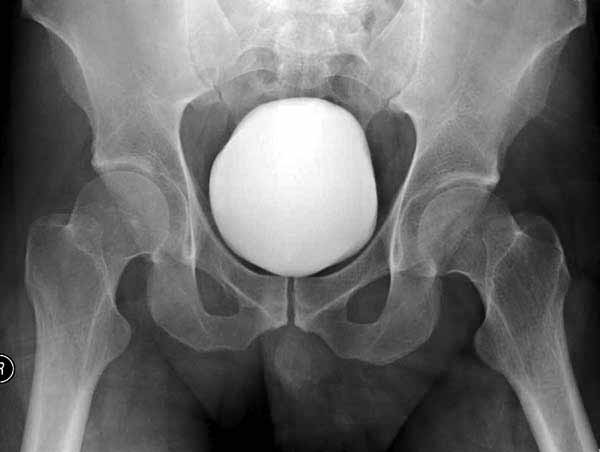

Имя     : 2-6 Fem head  fx-dislocation.jpg

Тип     : image/jpg

Размер  : 18301 байтов

Описание: отсутствует

Url     : http://weborto.net:8080/pipermail/ortho/attachments/20111231/d311d17a/attachment-0012.jpg